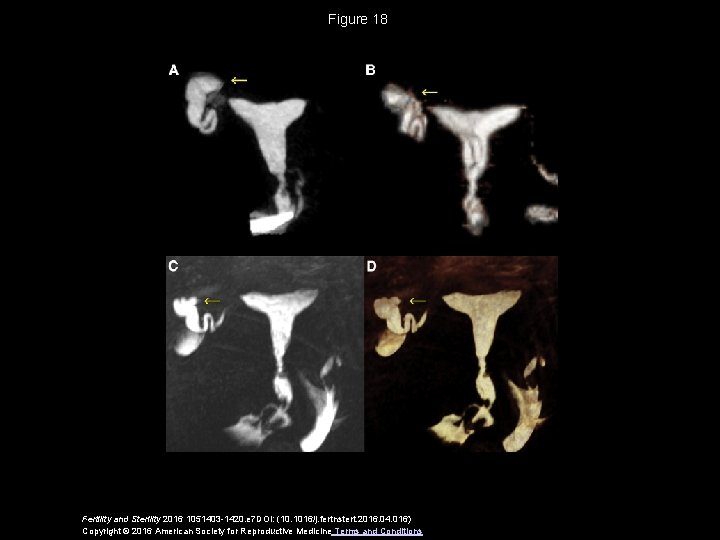

Figure 18 Fertility and Sterility 2016 1051403 -1420. e 7 DOI: (10. 1016/j. fertnstert. 2016. 04. 016) Copyright © 2016 American Society for Reproductive Medicine Terms and Conditions